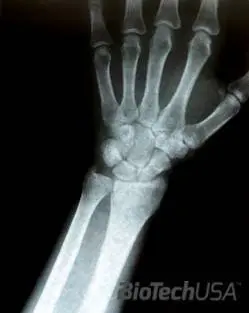

A törés jellemzője:/sites/testbiotechusashop/documents/news/_extra/1449/o_Fotolia_16628912_S_20130620140312.jpg

A sérült végtag duzzadt, nyomásra érzékeny, mozgatása fájdalommal jár. Sokszor szemmel látható a keletkezett deformitás ugyanakkor előfordul az is, hogy ezek a tünetek teljesen elmaradnak. Ebből kifolyólag a diagnózis felállításához szükség van röntgen vizsgálatra is, amelyet minden olyan baleset, sérülés után szükséges elvégezni, amelynél fennáll a csonttörés veszélye. Arra kell törekedni, hogy a csonttörést a lehető leghamarabb ellássák. Az ellátás módja orvosi elbírálás alá esik a törés fajtája, esetleges lágyrész sérülés függvényében, amely lehet gipszrögzítés, műtéti helyreállítás, külső vagy belső fémes rögzítés, stb.